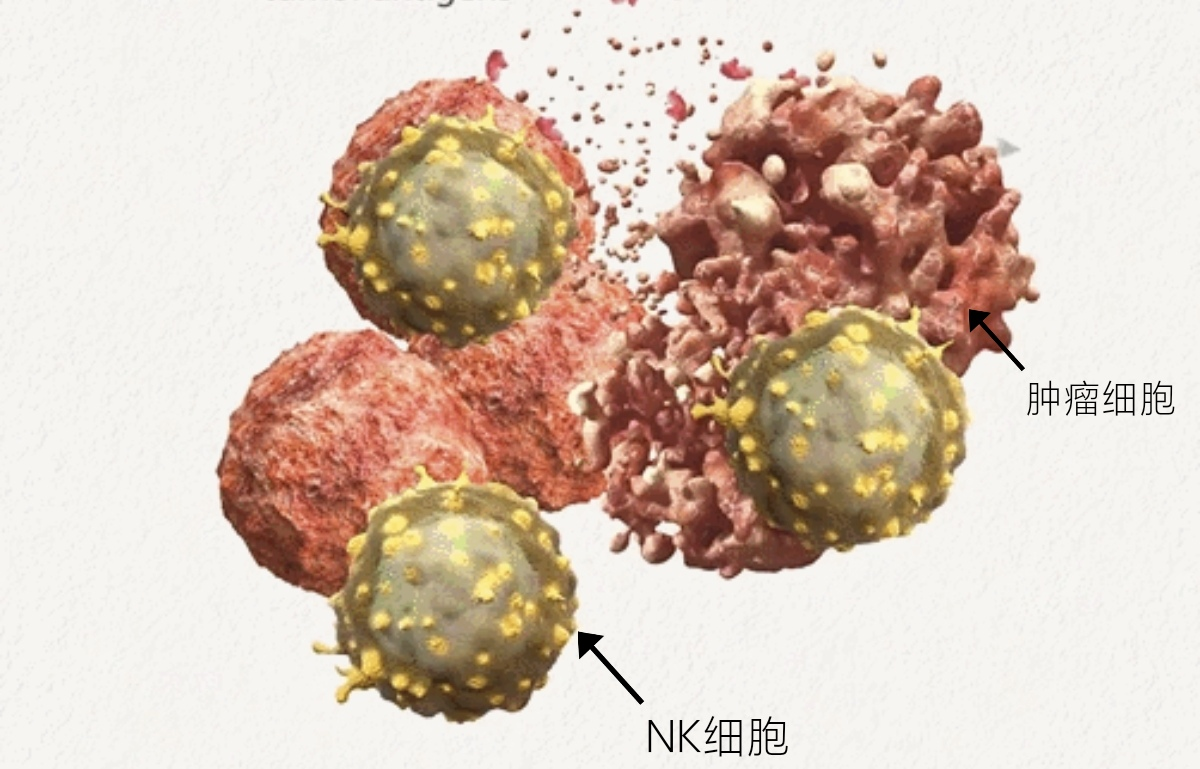

基于NK細胞的免疫療法

自然殺傷細胞(NK細胞)作為人體免疫系統(tǒng)抵御外來病原體侵入的第一道防線,在抵抗病毒感染和腫瘤的先天免疫和獲得性免疫防御中都發(fā)揮著重要的作用。近兩年來,NK細胞以其獨特優(yōu)勢逐漸成為腫瘤免疫治療中的新興主力軍,并在多種血液系統(tǒng)惡性腫瘤治療中展現(xiàn)出不俗的實力。

CAR-NK細胞療法

CAR-NK細胞療法也是通過基因工程的改造,將識別靶細胞(比如腫瘤細胞)表面抗原的抗體或受體與激活免疫細胞所需要的信號分子相連接,從而激活NK細胞,讓它對腫瘤細胞進行特異性攻擊。

NK細胞在惡性腫瘤的治療方面潛力高得令人難以置信,最近的研究結(jié)果表明,CAR轉(zhuǎn)導(dǎo)的NK細胞毒性低,且與高應(yīng)答率有關(guān),這充分說明了NK細胞作為潛在免疫療法治療患者的重要性。